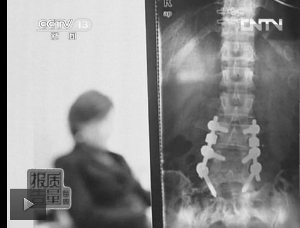

圖1:教練按壓導(dǎo)致學(xué)員腰椎間盤突出。(央視截屏)

無(wú)獨(dú)有偶,練習(xí)瑜伽受傷的現(xiàn)象,近幾年經(jīng)常出現(xiàn)在報(bào)道中。2011年,湖北一位女士因?yàn)榫氳べび龅剿浗叹?,竟然大腿骨折,最終瑜伽館承擔(dān)賠償責(zé)任;2010年,上海的鄭女士練瑜伽時(shí),因?yàn)榻叹毎磯憾鴮?dǎo)致腰椎間盤突出,如今,4顆合金鋼釘永遠(yuǎn)埋在她第4、5節(jié)腰椎上(圖1)。